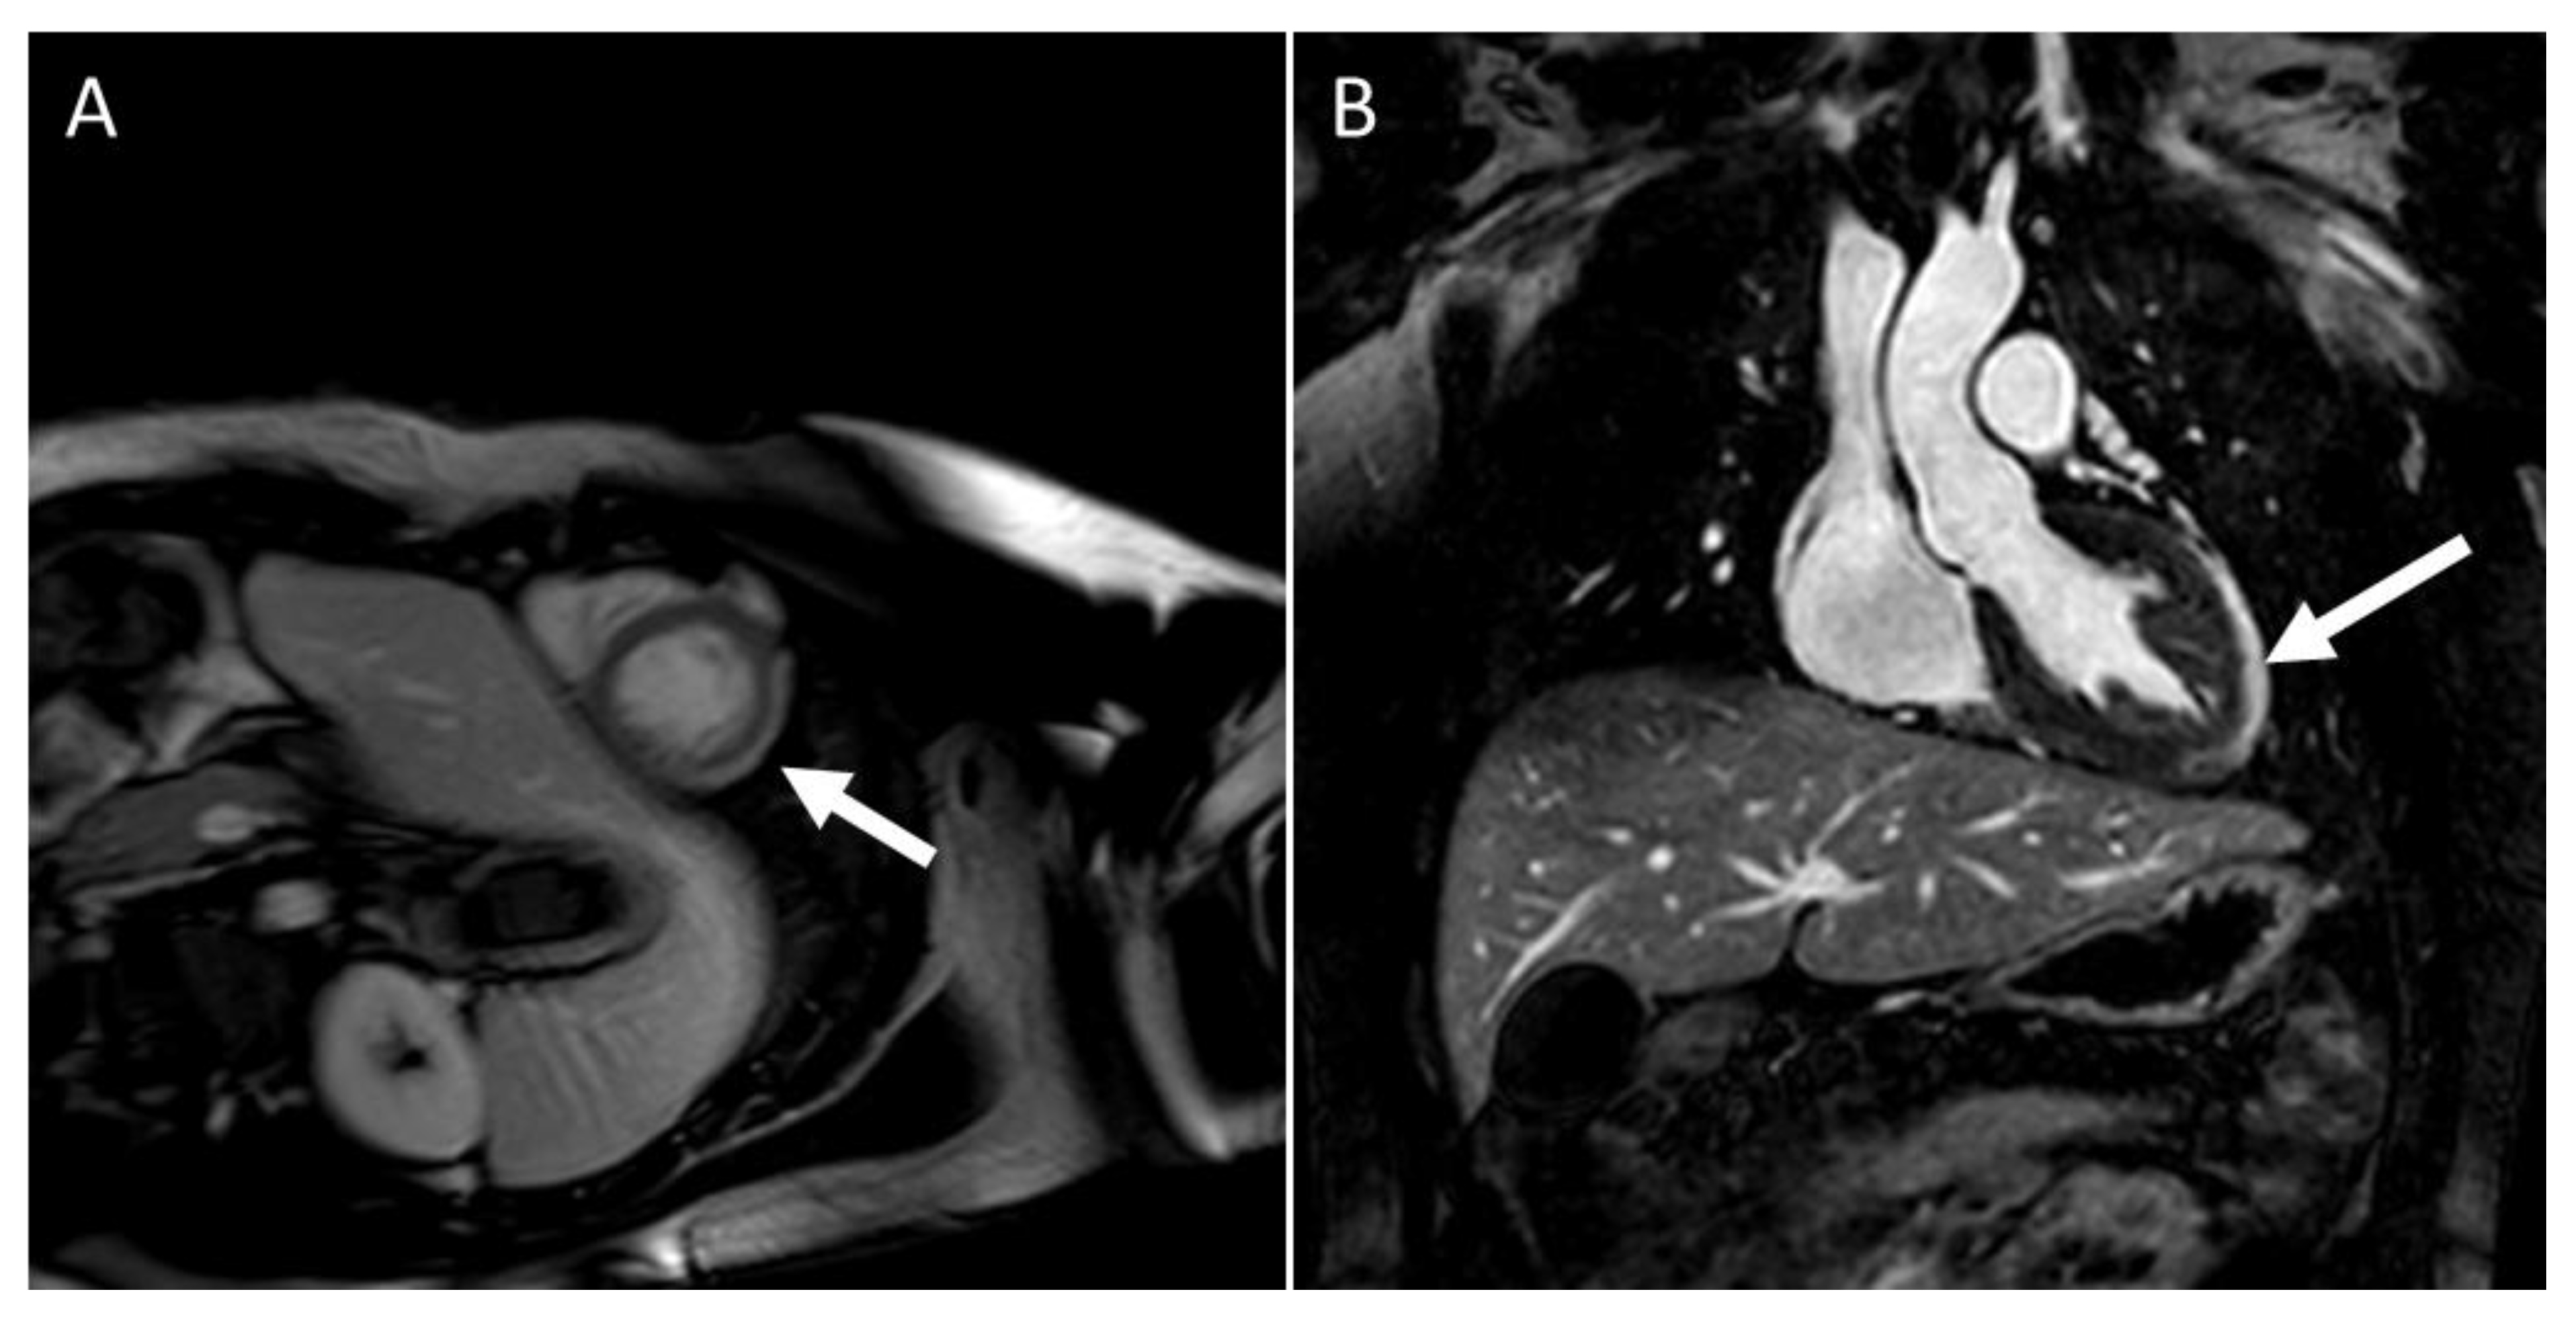

2. CMR Findings of Myocardial Inflammation and Pathological Correlations

3. CMR in Acute Myocarditis